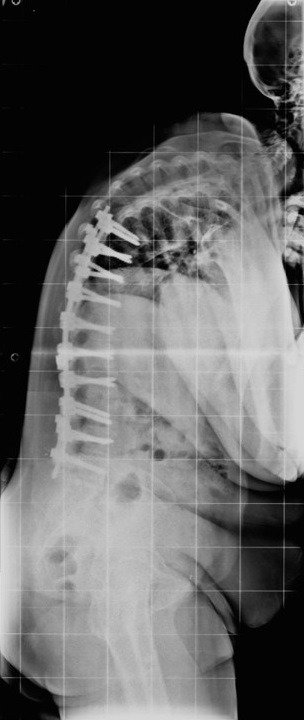

63 Yaşında Kadın Hasta

Ameliyat Öncesi